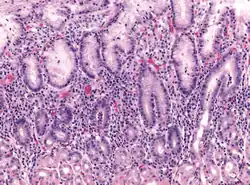

| Micrograph showing gastritis. H&E stain. | |